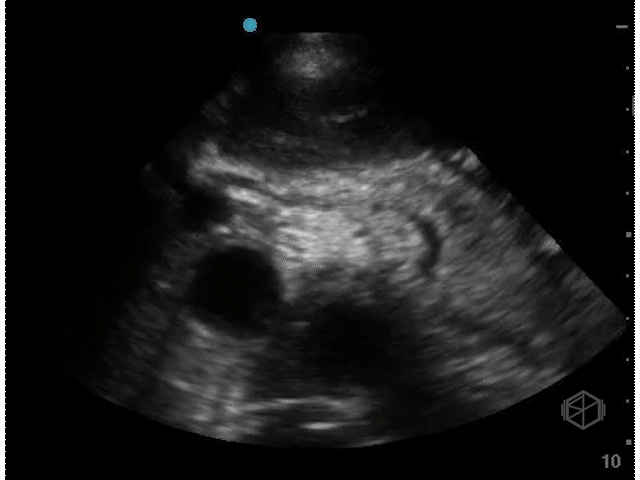

He was evaluating a 54-year-old male with a history of hypertension, hyperlipidemia, coronary artery disease, and current everyday smoking, who presented with shortness of breath. The patient was significantly hyperglycemic and was thought to be in DKA. He was also borderline hypotensive and there was a lacy appearance to his abdomen. The patient had a stat abdominal aorta scan that demonstrated the following:

There is a large circular anechoic structure in the middle of the scan. If you thought this was the abdominal aortic aneurysm — surprise — it’s not.

This a distended fluid filled stomach, a common false positive for FAST/FAFF examinations as well as aorta exams.

Patient had a CTA that demonstrated a normal aorta as well as diffuse gaseous distention of the esophagus mild/moderate gastric distention with fluid and gas due to recent alimentation.

• This structure seems to be coming from the left upper quadrant, with no vertebral body behind it and no IVC next to it. The color doppler signal is unreliable due to the patient’s heavy breathing.

• The stomach will appear as a cystic organ when distended with fluid. If there is clear fluid there may be echogenic gas bubbles visible (28191199). There many hints that the object in Dr. Nkemakolam’s case is the stomach and not the aorta.